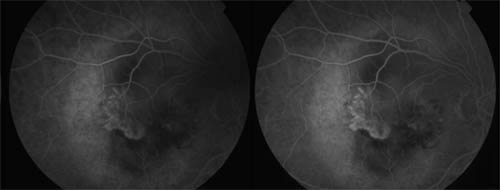

Fluorescein angiogram showing choroidal neovascularisation the "wet" form of age related macular degeneration